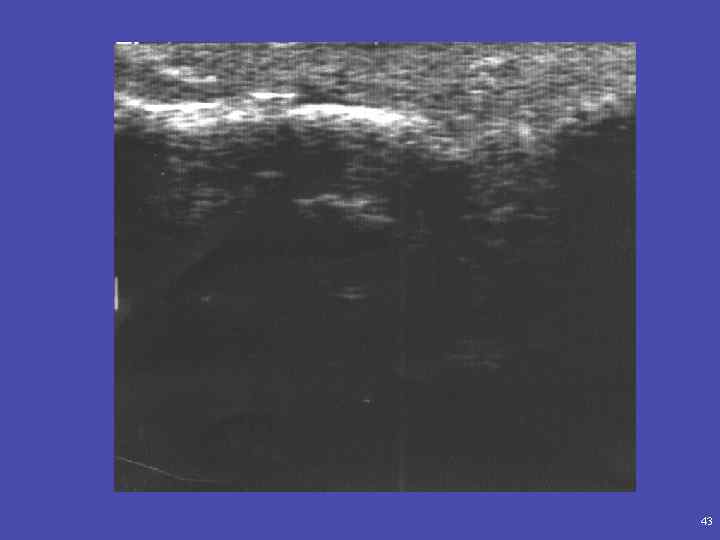

42

43